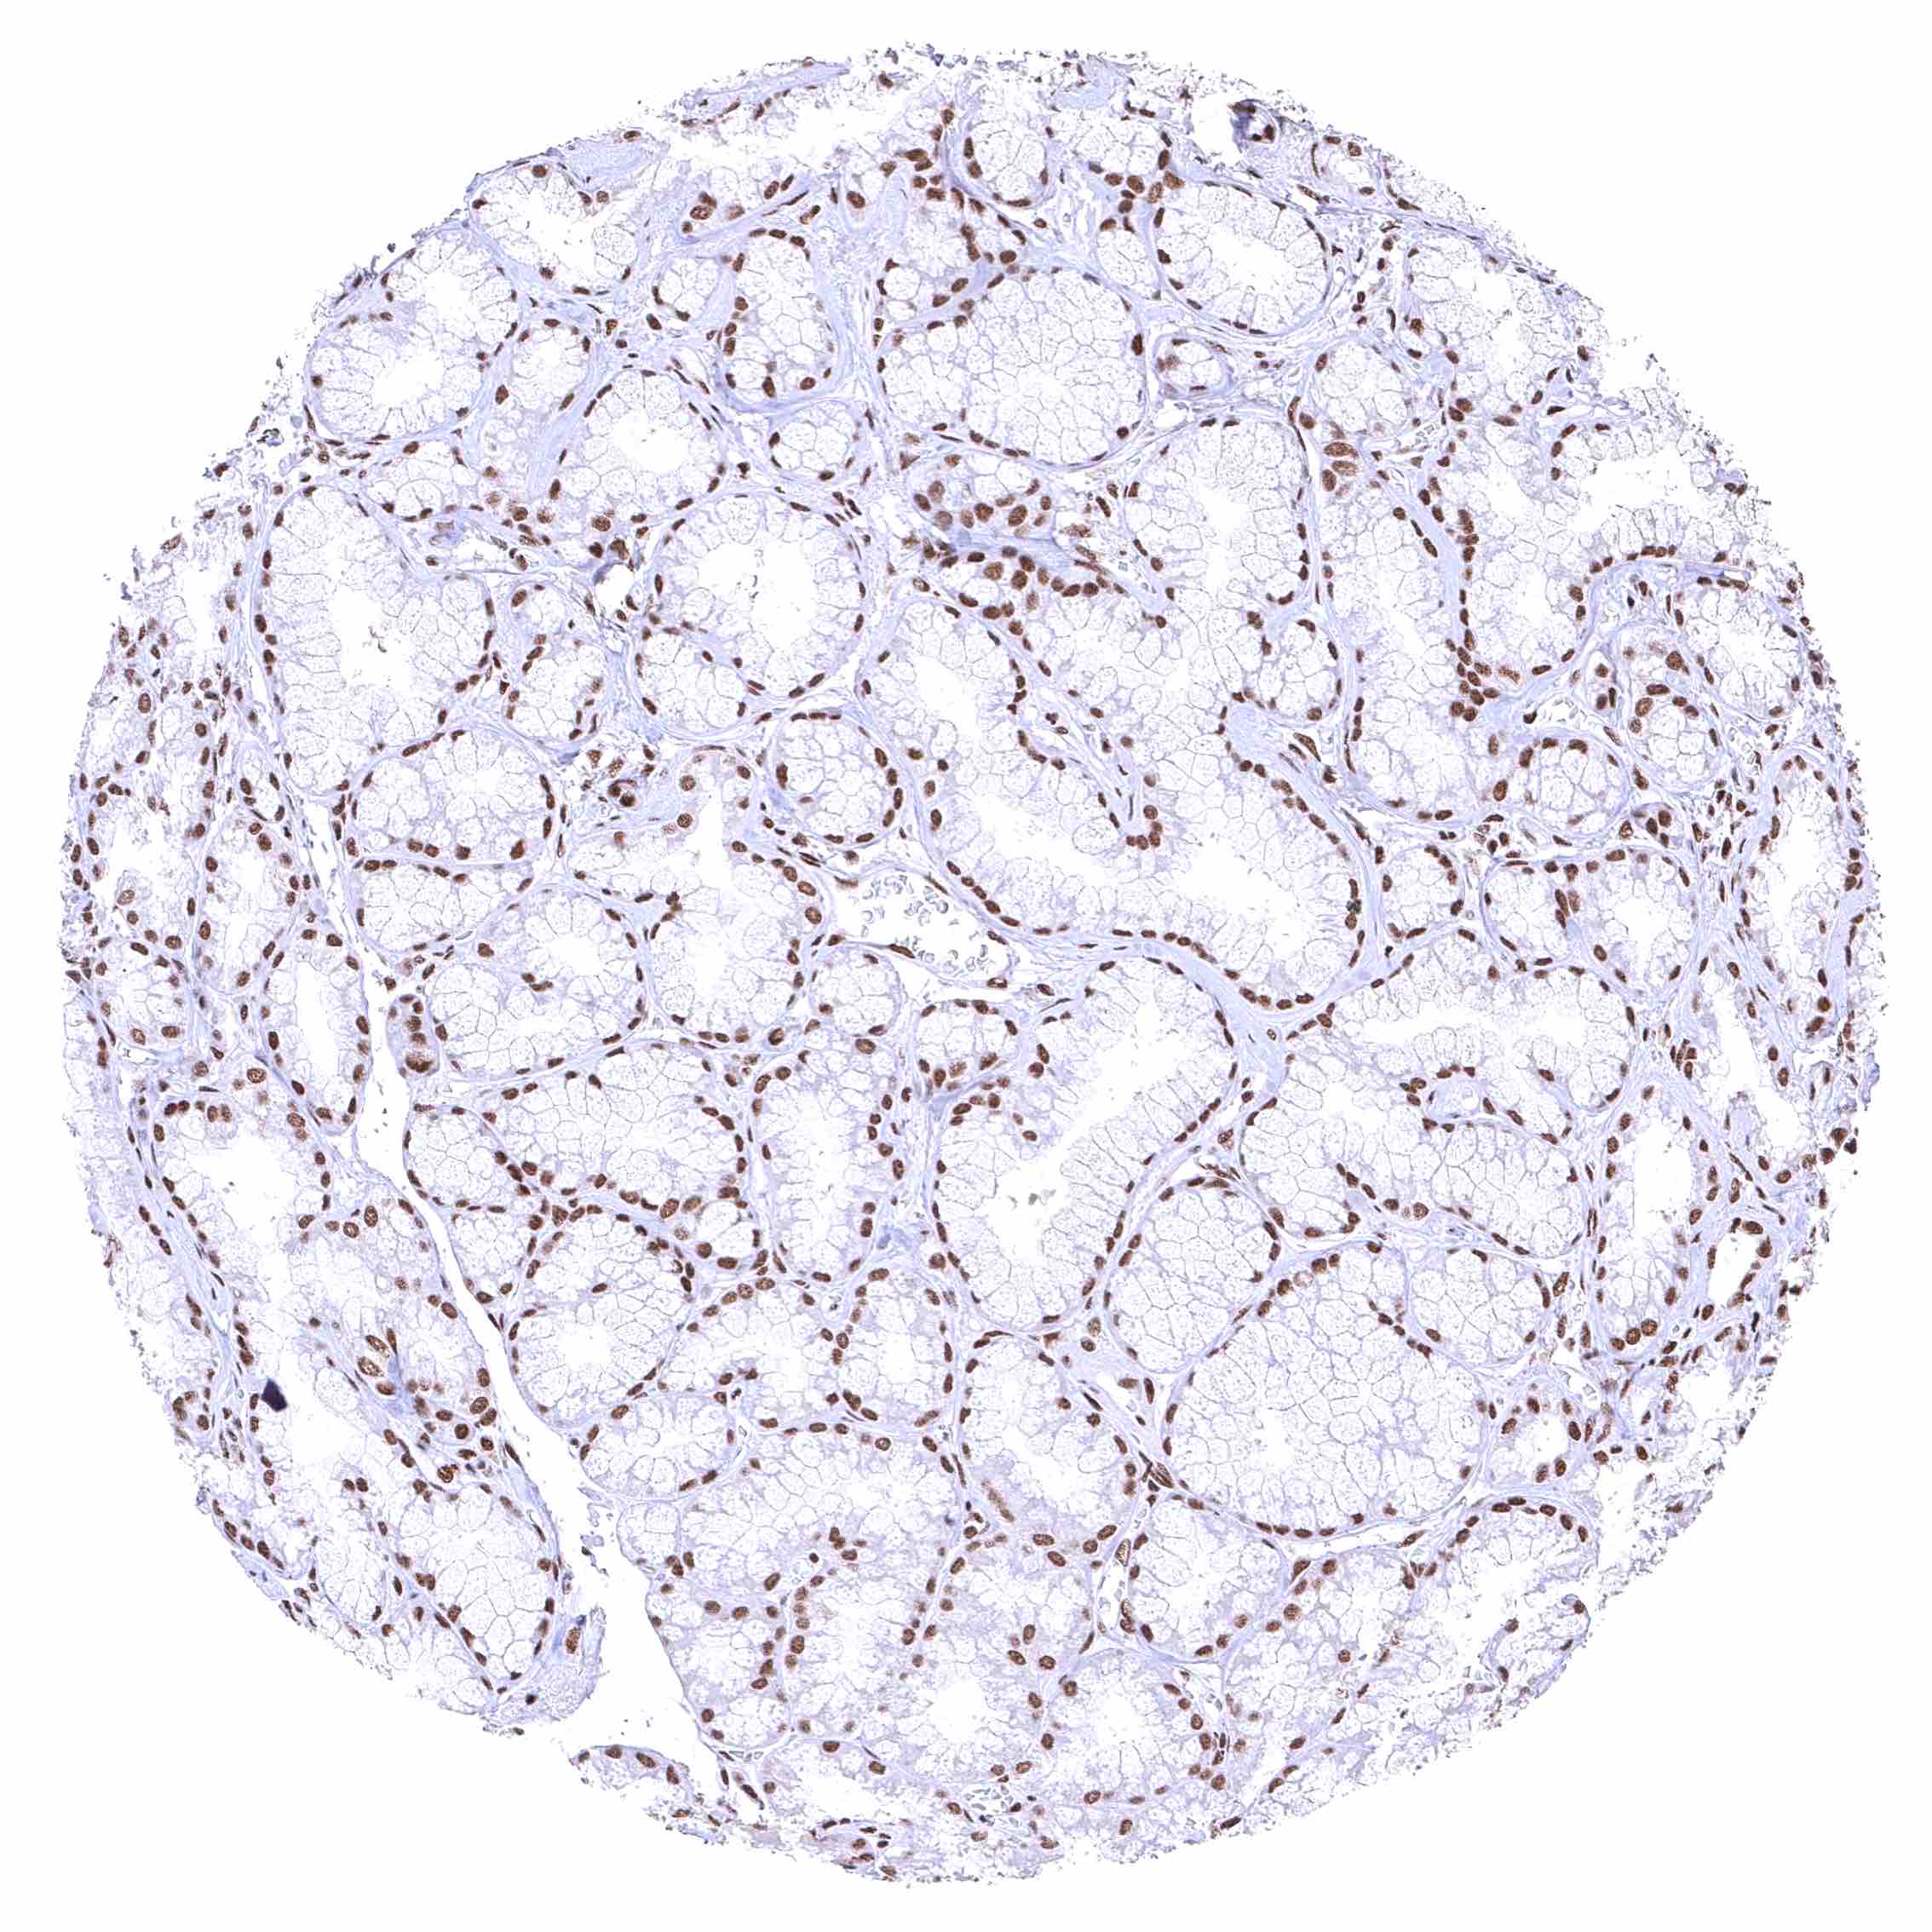

Placenta, early – Nuclear BRD4 staining is particularly strong in all trophoblast cells.